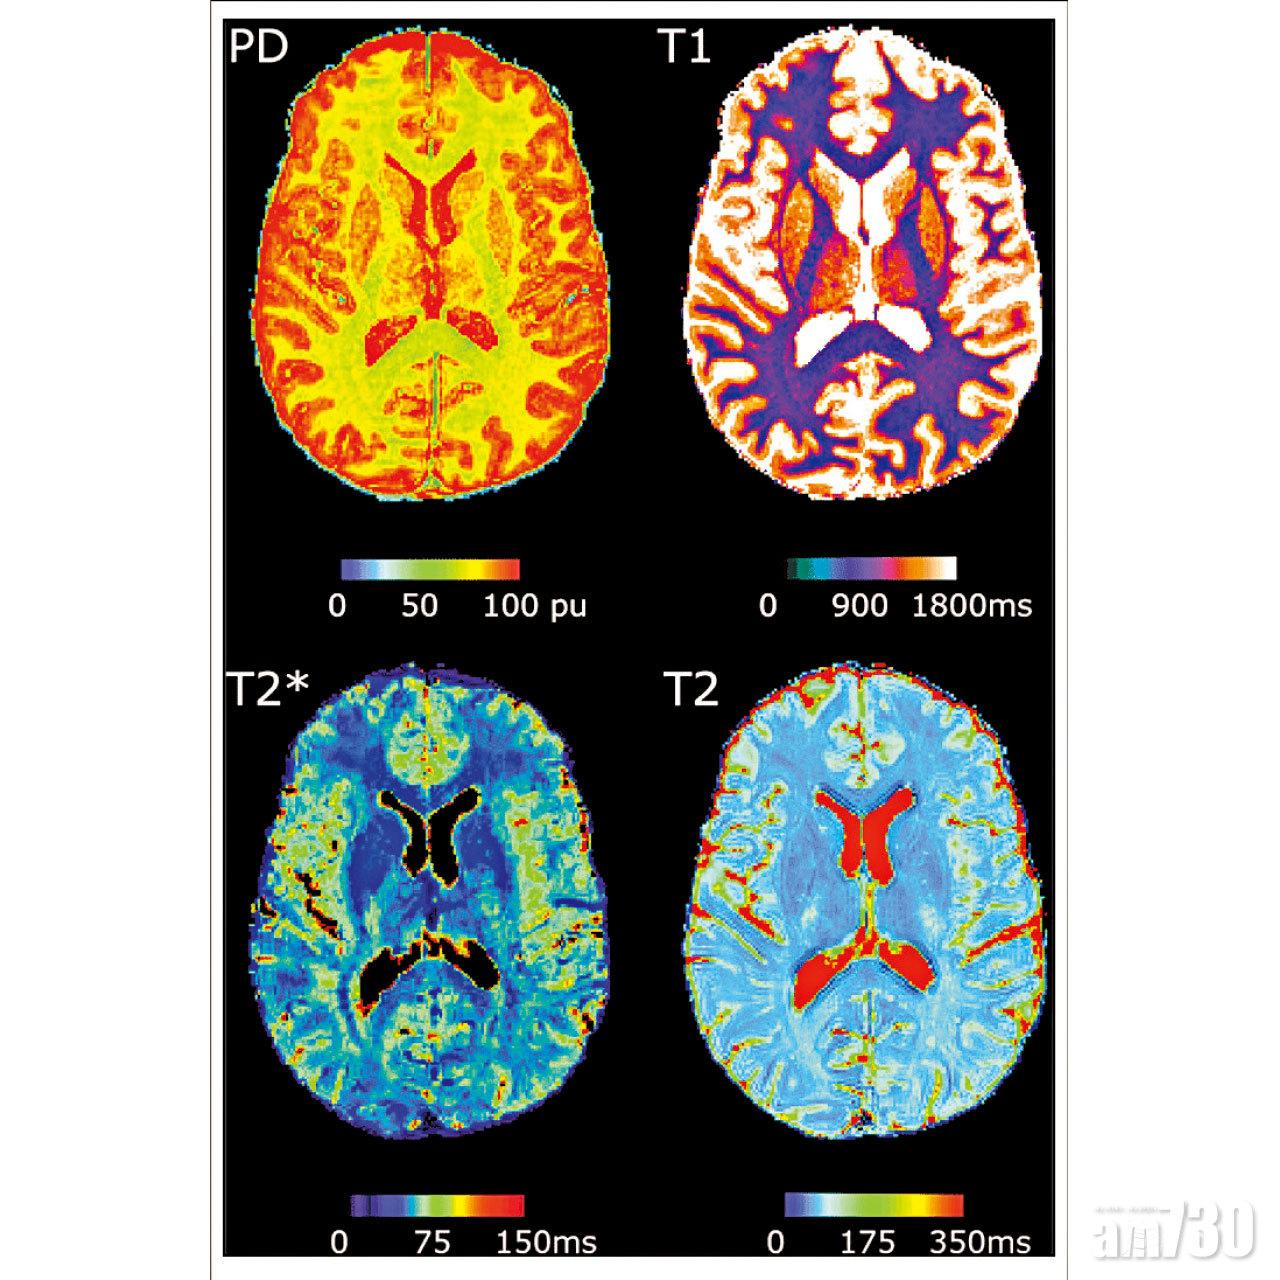

新一代的「量化磁力共振技術」(Quantitative MRI),是目前影像技術中的一個重要研究領域,可以直接獲取正常和病變組織的物理化學特徵參數。目前科學家仍在探索量化磁力共振技術在臨床疾病診斷中的應用,有海外研究則發現這項技術可有助準確診斷出阿茲海默症、認知功能障礙、乳腺腫瘤和前列腺癌等疾病。以美國凱斯西儲大學為例,研究團隊利用了自己提出的一種稱為「磁力共振指紋」(Magnetic resonance fingerprinting)的量化成像技術,去掃描並準確診斷出前列腺癌患者。

這類研究雖然處於早期階段,但目前的結果揭示了一個美好的未來,也就是磁力共振技術會從非定量的影像技術,發展成一種結合物理化學參數的影像技術,進而提高醫學影像診斷的準確性。